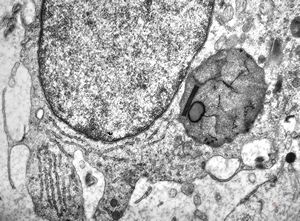

M,10y. | herpetic encephalitis